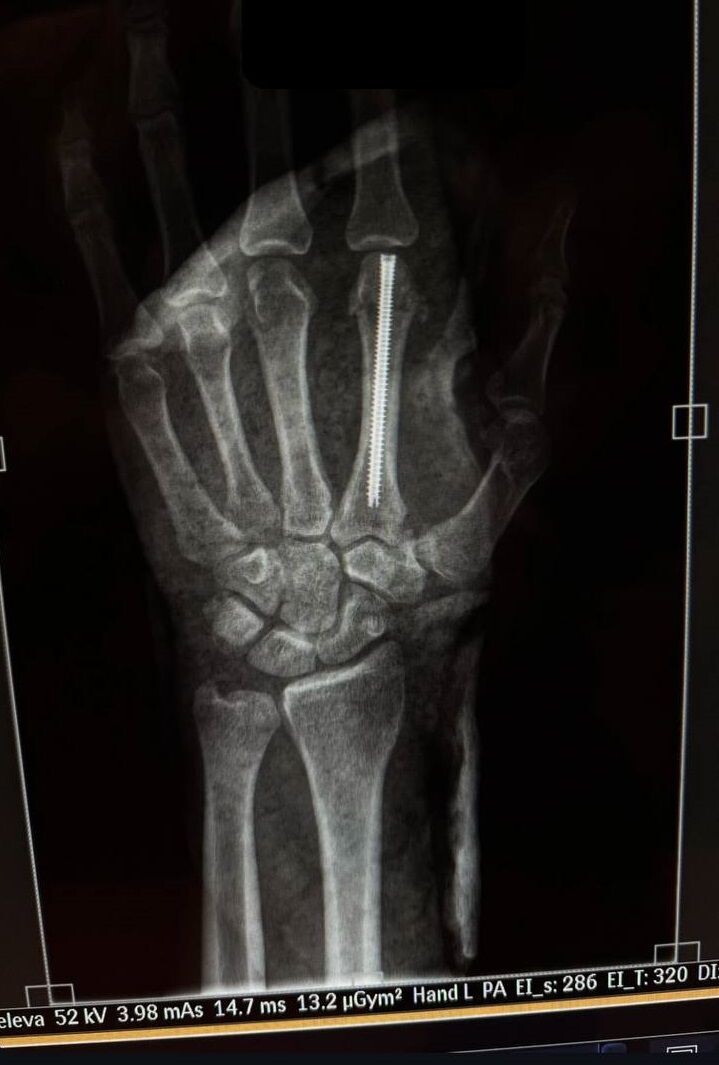

Умар Нурмагомедов показал рентген сломанной руки после операции

Бывший претендент на титул UFC в легчайшем дивизионе (до 61 кг) россиянин Умар Нурмагомедов опубликовал рентгеновский снимок своей руки после операции. Напомним, Нурмагомедов, проигравший единогласным решением действующему чемпиону грузину Мерабу Двалишвили на турнире UFC 311, сломал левую руку в первом раунде. Умару Нурмагомедову 29 лет. Россиянин дебютировал как профессионал в 2016 году и в январе 2021-го провёл свой первый поединок в UFC. Поражение от Двалишвили стало для уроженца Дагестана первым в карьере.